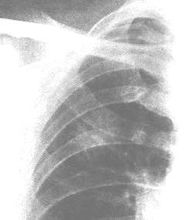

在無症狀的病人,胸部X線常可見一個外周性小結節性腫塊。如腫塊直徑<5~6mm,則難以發現。以往的X線檢查結果對了解新生物頗有價值。對較小的孤立結節,穿透性強的X線和體層攝片可顯示鈣化,鈣化的數量必須超過一個斑點,才能診斷為良性腫瘤或慢性肉芽腫性病變並排除肺癌。CT可顯示其他技術看不到的病變,並可根據有無淋巴結擴散的跡象有助於腫瘤的分期。偶爾需要胸部磁共振成像(MRI)檢查,對顯示肺尖Pancoast瘤有無胸壁及椎體侵犯最有幫助。

有症狀的病人,胸部X線可顯示支氣管狹窄和不規則肺實質浸潤,或肺不張。在阻塞區或在周圍型腫瘤內部可能看到空洞形成。阻塞性肺氣腫不常見。偶爾,X線可顯示在不相鄰的肺葉內有浸潤或阻塞區,此種現象不能用單個腫瘤灶解釋而是支氣管樹瀰漫性黏膜下淋巴滲透的結果。胸膜滲液往往與浸潤性或外周部腫瘤有關,胸液的細胞學檢查或胸膜活檢可提供診斷。極少數情況下,在尚未發現肺內病灶時,痰中即可找到腫瘤細胞。